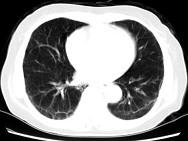

问题 女,35岁,咳嗽,咳痰,发热3月余,胸部CT如图,最可能的诊断为 ( )

选项 A.类风湿肺炎 B.红斑狼疮性肺炎 C.间质性肺炎 D.肺结节病 E.肺部感染

答案 C